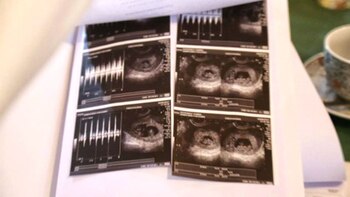

Yanina Gutierrez y Matías Graf viven en Tierra del Fuego y en julio se enteraron de que serán padres por primera vez. Pero el mismo día que confirmaron la noticia, el médico les comunicó también una novedad que haría de su embarazo un caso sin precedentes: tras someterse a la ecografía, el obstetra les dijo que esperan gemelos y mellizos a la vez.

"Sos la reina madre de la familia", le dijo con asombro el doctor a Yanina después de practicarle el estudio. La ecografía permitió observar que en el vientre de la madre hay tres bolsas. Una alberga a los gemelos y las otras dos a cada uno de los mellizos. "Es muy loco porque de ser dos pasamos a ser seis", señaló la mujer a Cadena 3 y resaltó: "estamos felices". "Yo veía tres bolsitas pero como es la primera vez que transitamos esto no sabíamos de qué se trataba, por eso nos quedamos callados", agregó.

Fue entonces que les informó del múltiple embarazo. "'Quedate tranquila, ¿Tu familia es descendiente de mellizos?', me preguntó y para ese momento nosotros ya estábamos emocionados y contentos porque sospechábamos de que íbamos a tener dos. Y, el médico me dijo: 'No, son más'. ¡Trillizos!, pensamos nosotros y el doctor nos terminó confirmando: '¡Son cuatro: en cada punta están los mellizos y en el medio los gemelos! "Nos hizo sentir el corazón de todos", relató la joven.